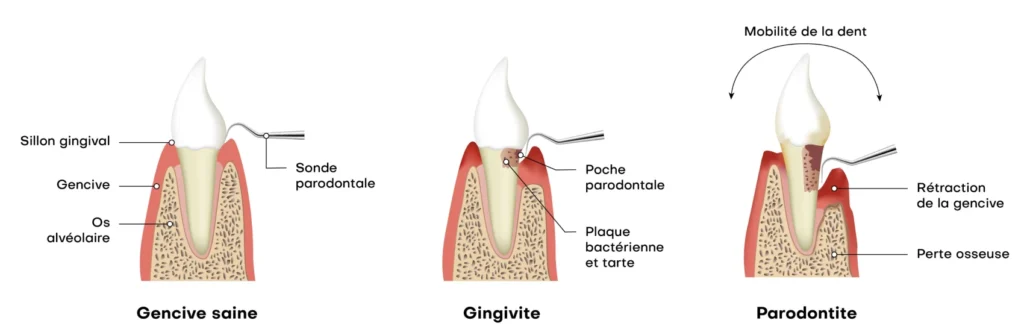

La parodontologie concerne les tissus qui soutiennent les dents. Elle inclut la gencive, l’os et le ligament parodontal. Cependant, une inflammation peut s’installer durablement. Ensuite, des poches se forment entre la dent et la gencive. Ainsi, les bactéries deviennent plus difficiles à éliminer.

La parodontite détruit les tissus de soutien. Cependant, elle progresse parfois sans douleur. Ensuite, des poches profondes apparaissent. Ainsi, le nettoyage devient difficile.

Certaines poches restent profondes malgré le traitement initial. Ensuite, l’inflammation continue. Ainsi, une chirurgie peut aider à assainir la zone. Cependant, l’indication dépend de plusieurs critères.

La gencive peut se rétracter et exposer la racine. Ensuite, la dent devient plus sensible. Ainsi, le risque de carie radiculaire augmente. Cependant, une prise en charge peut stabiliser la situation.